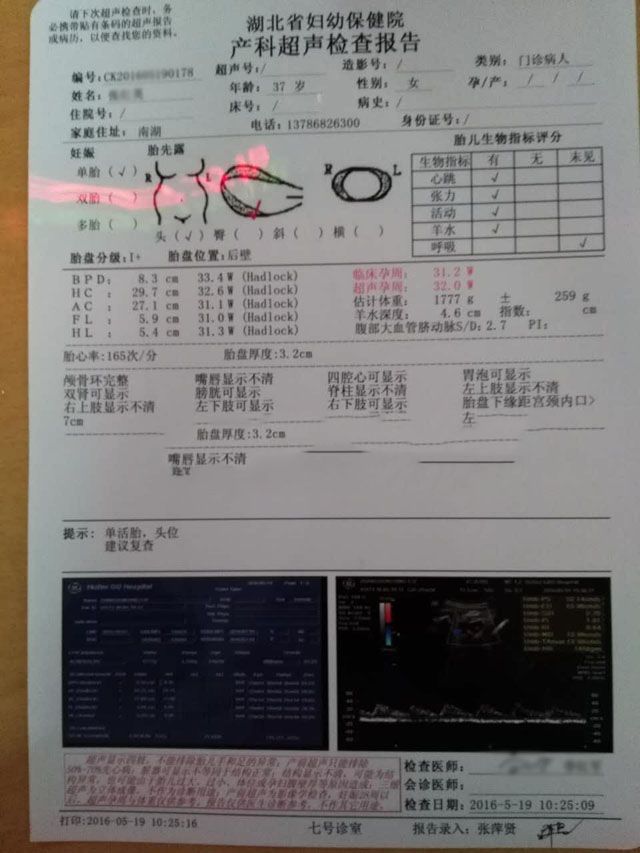

要不要看看产检记录!

2016年7月4日,孕37周,男宝宝顺利降临。